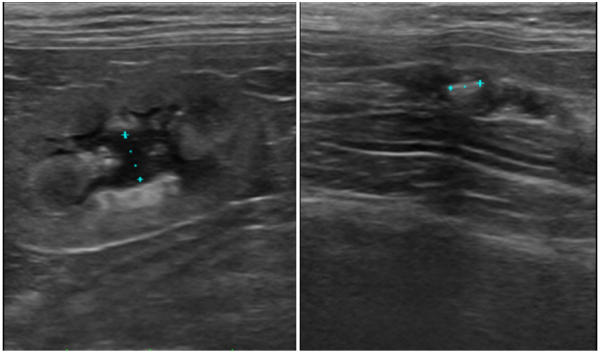

정확한 진단을 위해 초음파 기반의 영상검사를 실시하였으며,

이를 통해 요관결석과 요관폐색 여부를 확인하였습니다.

검사에서 좌측 요관결석이 확인되었고,

시간이 지나며 요관이 완전히 막히면서

심한 수신증으로 급격히 악화되었습니다.

초음파 검사에서 방광의 심한 팽만과 함께 요도가 전반적으로 확장되어 있고,

요도 원위부 내 다량의 사결석과 결석이 관찰되었습니다.